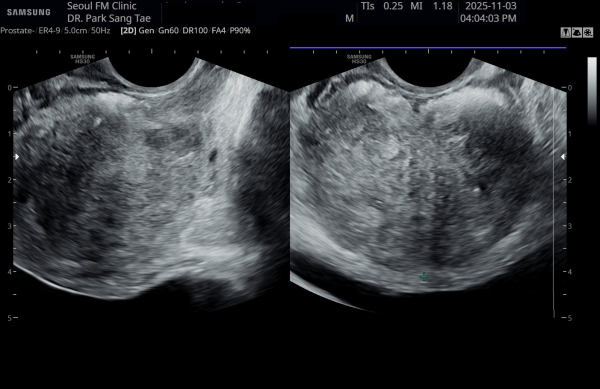

17개월동안 상급 의료 기관에서 전립선 치료에 대한 투약을 했으나 증상의 호전이 없이 배뇨장애와 배뇨시 통증으로

내원 당일 경직장 전립선 초음파 사진상 전립선내 거대 농양이 관찰되는 자료입니다.

"A transrectal prostate ultrasound image taken on the day of the visit, showing a large prostatic abscess in a patient

who had been receiving prostate treatment with medication at a higher-tier medical institution for 17 months without symptomatic improvement,

experiencing voiding dysfunction and pain during urination."